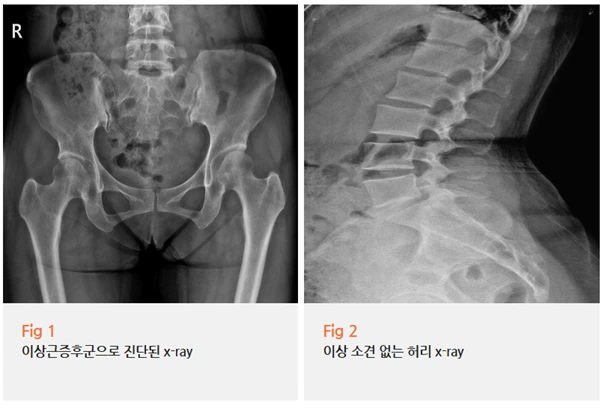

오늘은 최근 제가 직접 진료했던 환자분 사례를 중심으로

이상근증후군에 대해 이야기해보려 해요.

작년 겨울, 엉덩방아를 찧은 후 시작된 통증

40대 여성분이었는데요.

✅ 엉덩방아를 찧은 외상 이력

✅ 오래 앉았다 일어날 때 특히 심한 통증

✅ 딱딱한 곳에 앉으면 더 아픈 증상

✅ 엉덩이에서 다리 뒤쪽으로 뻗치는 방사통

전형적인 이상근증후군 증상이었거든요.

사실 이상근증후군은 허리디스크와 증상이 정말 비슷해요.

둘 다 엉덩이부터 다리까지 통증이 뻗치니까요.

그래서 잘못 진단받는 경우가 생각보다 많아요;;